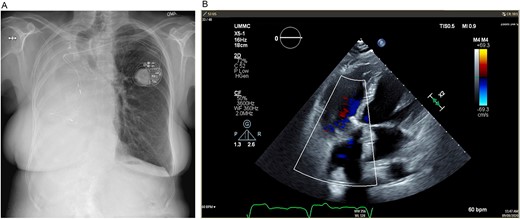

Mild–moderate TR was first noted on transthoracic echocardiogram 5 years after pneumonectomy and continually worsened over the next 10 years until she had wide open severe TR with moderate RV dilation and moderate global reduction in RV function. After multidisciplinary evaluation, TVR was recommended. Preoperative imaging revealed notable mediastinal shift to the right, severe counterclockwise rotation and displacement of the heart to the right and expansion of the left lung into the right hemithorax (Figs 1 and 2).

(A) Preoperative posteroanterior view chest X-ray showing left to right mediastinal contents shifted and a clear left lung. (B) Preoperative transesophageal echocardiogram with doppler showing severe tricuspid regurgitation with no coaptation between the anterior and septal leaflets.